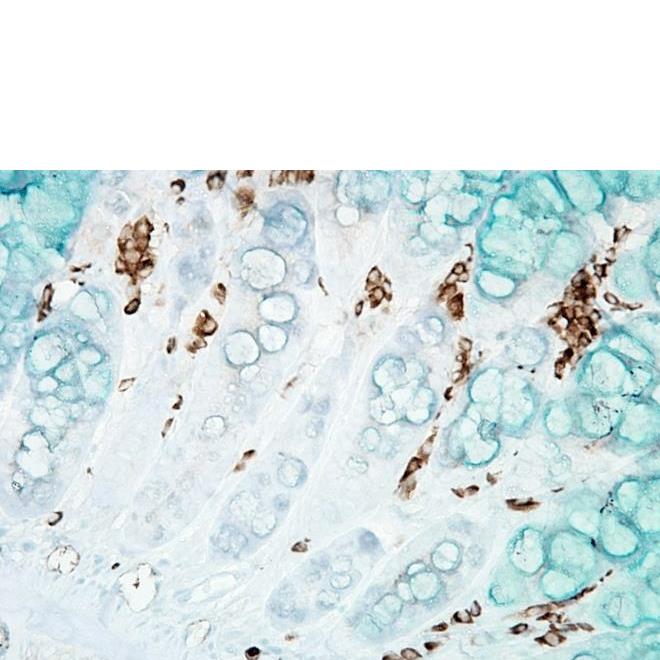

产品名称:Anti-DNA/RNA Damage Antibody 15A3抗体

Anti-DNA/RNA Damage Antibody 15A3抗体

产品名称 | DNA/RNA 损伤(8-OH-dG)抗体 |

产品描述 | 小鼠抗DNA/RNA 损伤(8-OH-dG)单克隆IgG2b |

适用物种 | 与物种无关 |

应用范围 | IHC, ICC/IF, ELISA, DB, IP, FCM, FA |

稀释度 | IHC (1:1000); 用户需根据具体情况决定的稀释度. |